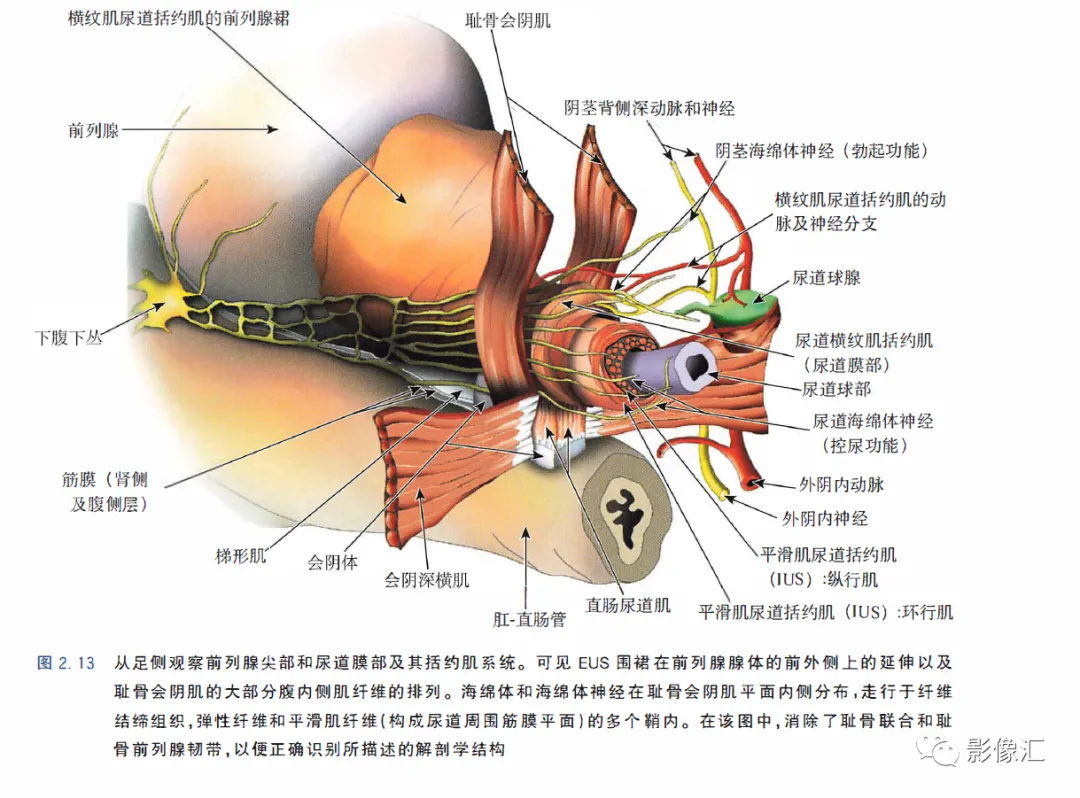

前列腺尖部是用于表示前列腺腺体尾侧(最下方)的术语,与尿道膜部密切接触。前列腺尖部可显示出不同的形态:圆环形或腹侧,背侧或两侧突出(图2. 9和图2.10) ,了解前列腺尖部形态的重要性主要在于两点:(1)前列腺尖部或多或少与EUS(尿道膜部的横纹肌纤维)头侧区域重叠(或覆盖),这些纤维部分融入前列腺尖部(图2.11)。在接受根治性前列腺切除术的患者中,有必要采用能够外翻(exteriorising)和解剖这部分横纹肌纤维的手术技术, 以保持控尿功能(图2.12)。(2)在根治性前列腺切除术中必须避免阳性边缘 。值得注意的是,在尖部水平,腺体组织仅为外周带组织,尖部仅前缘一小部分为AFMS。此外,前列腺尖部构成所谓的梯形区域的顶部,这是众所周知的解剖薄弱区域,在该区域前列腺癌可更易侵犯至前列腺间隙(图2.8)。在其前外侧,前列腺尖部由外括约肌群覆盖,与AFMS及从膀胱颈延伸来的由平滑肌构成的逼尿肌群相融合(图2. 13)。前列腺尖部尾侧与尿道膜部起始部相延续。男性的尿道膜部被认为是位于前列腺尖部和尿道球部之间的尿道部分,长度约为1cm。其内有尿道内括约肌(IUS)和尿道外括约肌(EUS)。IUS从膀胱颈(此处最厚)延伸到尿道球部,沿尾侧方向厚度逐渐减小。IUS环尿道膜部,由双层平滑肌纤维组成,包括内层纵行肌和外部的环形肌(图2. 13和图2. 14)。IUS的神经支配来自自主神经、交感神经和副交感神经系统。下腹下神经丛负责前列腺、前列腺尖部和尿道膜部的所有自主神经支配。其终末支沿内侧走行达耻骨上肌,外侧走行达尿道膜部的EUS,在腹侧构成所谓的阴茎海绵体神经(负责勃起机制)和尿道海绵体神经(负责尿道膜部黏膜的自主神经传入,直接与控尿机制有关(图2 . 13 和图2. 14)。EUS构成横纹肌平面(横纹肌纤维),在尿道膜部水平围绕IUS,在前列腺尖部的前外侧上扩展,并在该水平上构成所谓的EUS围裙(图2. 13)。其肌纤维主要是I 型(即没有肌梭),尽管强度低,但专门负责长时间收缩。EUS的功能在于排尿间期保持尿道腔塌陷,从而防止无意识的尿液渗漏。EUS最厚处位于尿道膜部水平,厚度向头侧逐渐减小,最终构成前列腺围裙。该围裙以Ω(希腊字母“欧米伽”)形围绕尿道膜部,而后正中不包绕, 形成“后正中脊”(图2. 13 和图2. 14)。此外,EUS的部分横纹肌纤维融入到前列腺尖部的下部,位于精阜下方,融入纤维的多少依赖于前列腺尖部形态(图2. 11) 。EUS的神经支配和动脉供血分别来自外阴神经和外阴内动脉。该神经为躯体神经,因此EUS可随意控制。外阴内神经和动脉均向头侧走行,至会阴深横肌处,发出分支支配EUS最尾侧部分,随后形成阴茎背侧神经脊背侧动脉。前列腺尖部与支配EUS的外阴内动脉的分支之间距离为3~13mm (图2. 13)。IUS和EUS构成所谓的控尿被动及内在因素。它们的功能基本上是“塌陷”尿道至“后正中脊”,这样可防止排尿间期无意识的尿液“泄露”(图2.11和2.13)。阴茎海绵体神经在前列腺周围筋膜的后外侧及前外侧走行。手术操作时保留这些外侧神经对于确保前列腺根治术后勃起功能的恢复是至关重要的。会阴体是一纤维肌性结构,难以在解剖上进行评估,其功能是支持所有构成会阴部及支撑盆腔脏器的肌肉及腱膜结构。对于控尿,会阴体形成一固定的底盘,通过将EUS的横纹肌平面压至底盘处,从而可使EUS正确发挥功能,这样在排尿间期可以正确地使尿道塌陷。会阴体由以下结构组成(图2.13)和图2.14)。

肛提肌与尿失禁的外在因素(主动因素)相关。肛提肌由两个肌肉平面组成,即耻尾肌和髂尾肌。耻尾肌起源于耻骨的中分支(mid-branch of the pubis),在肛尾韧带和尾骨的水平从背侧插入。耻尾肌的内侧纤维向内走行,在肛门直肠管的水平处构成肛门外括约肌后面的环,让直肠形成一定弯曲,有助于肛门压力和闭合机制。同时,耻骨直肠肌的内侧纤维向尾部中线移动,在尿道膜部以及前列腺尖部及其括约肌系统外侧走行,并在会阴体、肛门外括约肌的最深部分和尿道球部水平插入。这些肌肉纤维被称为耻骨会阴肌(也称为耻骨尿道肌或前列腺提肌)。耻骨会阴肌构成会阴底部的腹内侧部分,并且最终可以覆盖耻骨前列腺韧带的外侧表面,使得其更远端的纤维沿着平行于尿道膜部的平面走行。在大多数情况下,要完整保留这个肌肉平面。要求部分分离耻骨前列腺韧带,目的是可以找到正确的解剖平面进行手术切除(图2. 15)。MRI在评估前列腺尖部、尿道膜部和尿道括约肌复合体中的作用

根治性前列腺手术有两个主要目标:完全切除肿瘤和令人满意的术后功能,即控尿及阴茎勃起功能的恢复。为了在根治性前列腺切除术后实现早期控尿恢复,需要完全保留尿道括约肌系统,同时保留耻骨直肠肌和耻骨会阴肌(后者更为重要)。EUS的保存始于在腺体顶端前外侧上彻底分离EUS裙,向尾部方向操作。根据尿道周围筋膜,可正确识别和分离尿道膜部的EUS,这是阴茎海绵体和尿道海绵体神经未梢的位置(图2.12 至图2.14) 。AFMS和前列腺尖部的MRI评估可以显示这些区域中存在肿瘤,或者为主要病灶区域,或者更常见的是,MRI可以显示最初其他解剖区域的肿瘤对AFMS和(或)前列腺尖部的局部累及。这些情况下,在这个水平由于造成阳性切缘的风险很高,因此括约肌保留手术是禁忌的。